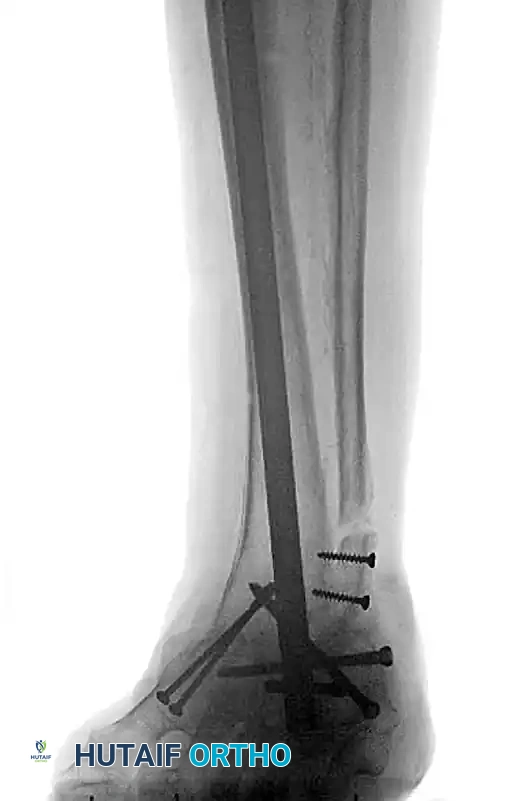

The following preoperative and postoperative radiographs demonstrate the successful application of augmented fixation in a young diabetic patient with a severe bimalleolar fracture-subluxation:

FIGURE 85-25 C-E: Postoperative fixation demonstrating robust fibular plating, medial malleolar screw fixation, and critical supplemental syndesmotic screws to reinforce the mortise.